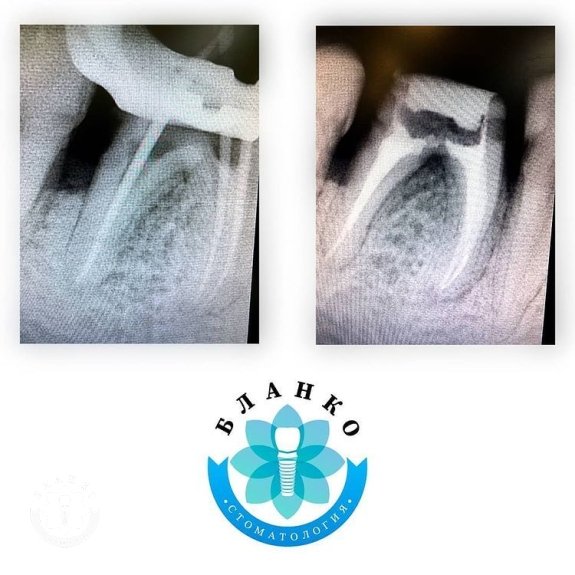

✳️На початковому знімку ми бачимо зуб 4.6 (обведений червоним кольором),в якому спостерігається хронічне запалення навколо коріння зуба та погана реставрація з пломбувального матеріалу, яка давно відійшла від тканин зуба і під якою розвинувся вторинний карієс (знімок №2).

- розпломбовані та проліковані кореневі канали

- запломбовані кореневі канали